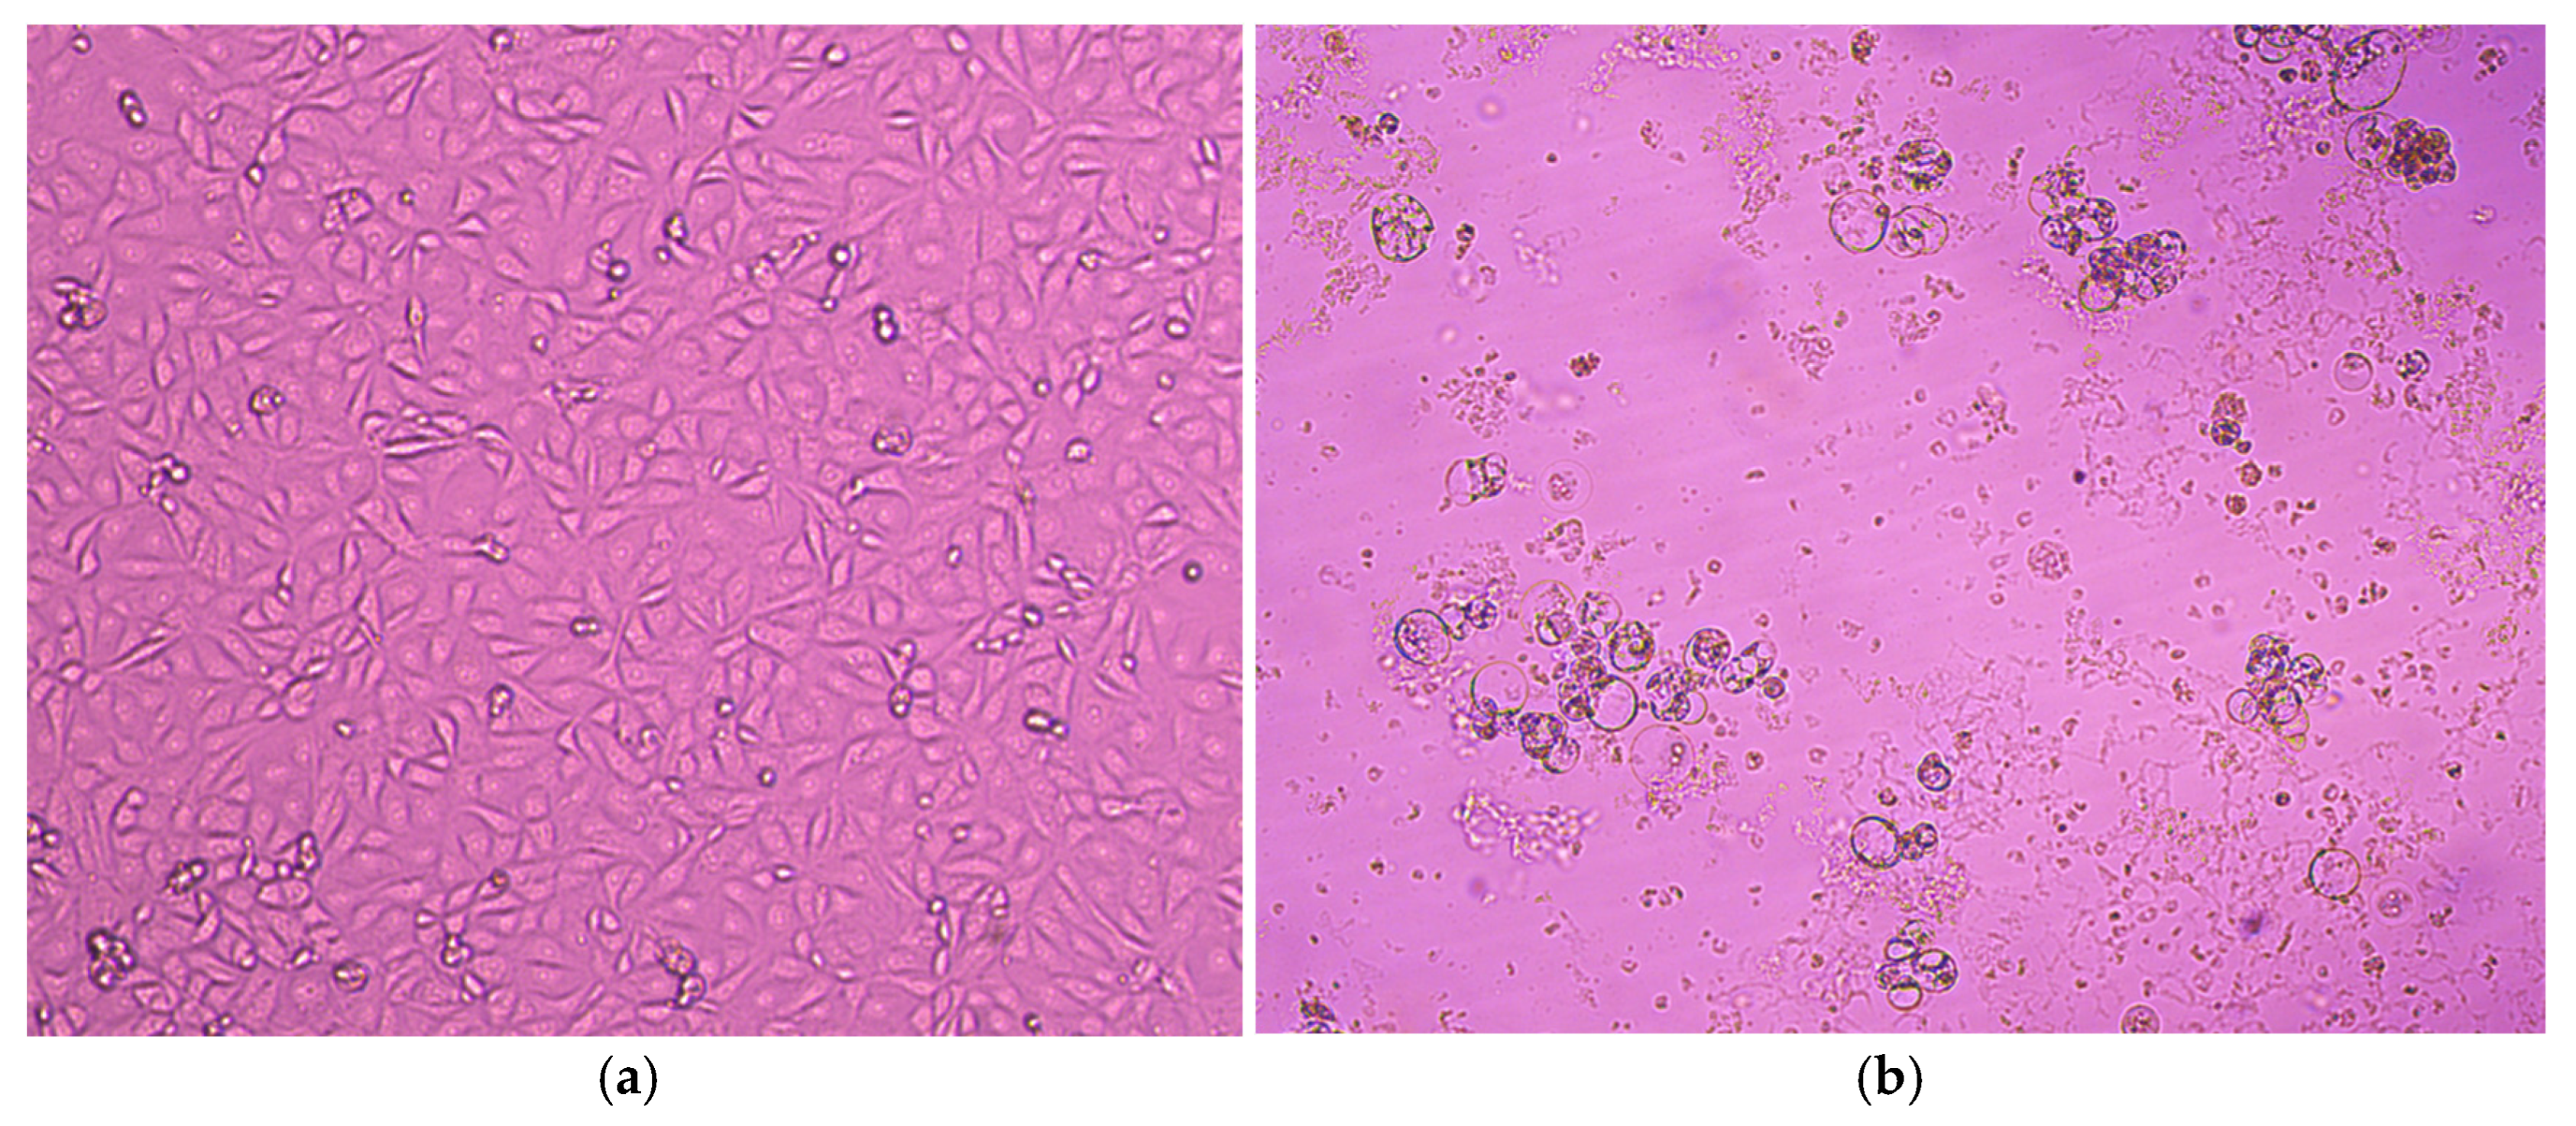

3.2. Virus Isolation on MA-104 and LLC-MK2 Cell Lines